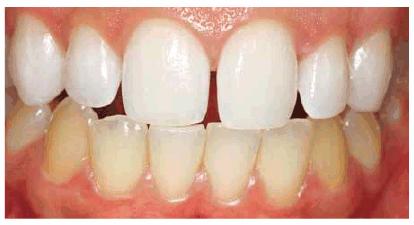

chromogenic foods, and beverages (Figures 16-16A 16-16B 16-17A, and 16-17B). Although these types of stains

generally require only 2 to 6 weeks of bleaching treatment, some are more

Figure 16-16A: Some teeth darken over time from chromagenic foods. Some patients' teeth are just naturally yellow.

Figure 16-16B: Whitening of the maxillary teeth using 10% carbamide peroxide in a custom tray results in a more pleasing smile. This patient is now interested in closing the spaces.